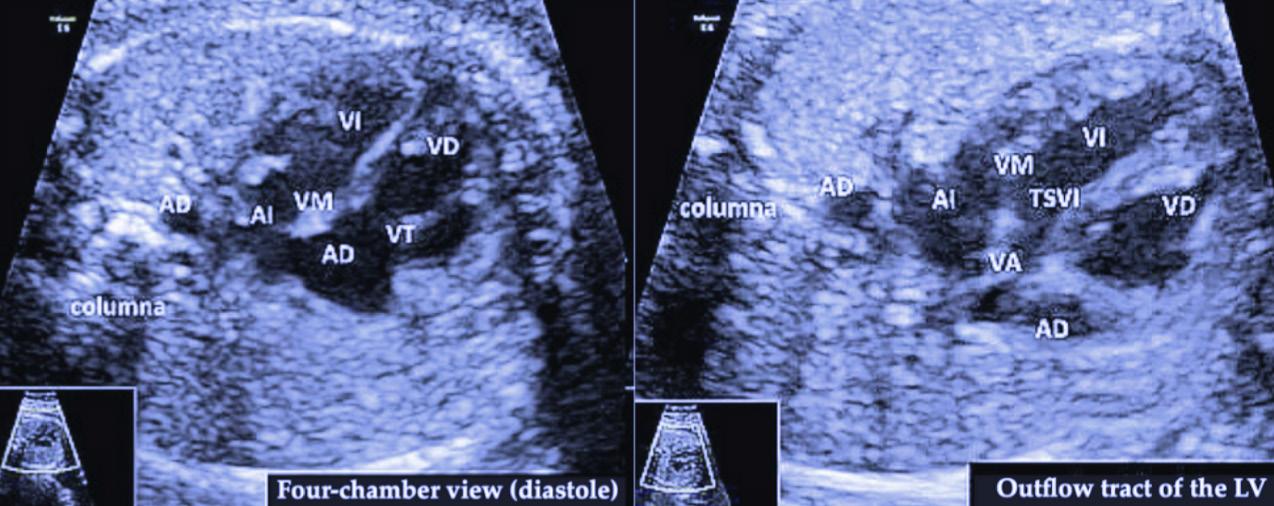

Opening Issue 46, editors Atta Yazdy, Emily Wang, and Kathy He transcend country borders to describe novel healthcare innovations, while Shehraz Riar and colleagues explore indicators of immune cell-based inflammatory ratios in acute coronary syndrome. Cynthia Duan, Nirujah Sutharsan, and Ruhani Khattra delve into N. fowleri, the brain-eating amoeba, while Prem Patel and Ciara Reid critically review pharmacologic interventions in neonatal seizures, and Hirday Josan and Miran Master discuss early detection in congenital heart defects.

OPTIMIZING EARLY DETECTION: A REVIEW OF PRENTAL DIAGNOSIS IN CONGENITAL

doi: 10.35493/medu.46.30

AUTHORS: HIRDAY JOSAN1 & MIRAN MASTER2

1 Bachelor of Science (Honours), Class of 2027, McMaster University

2 Bachelor of Health Sciences (Honours Biochemistry), Class of 2027, McMaster University